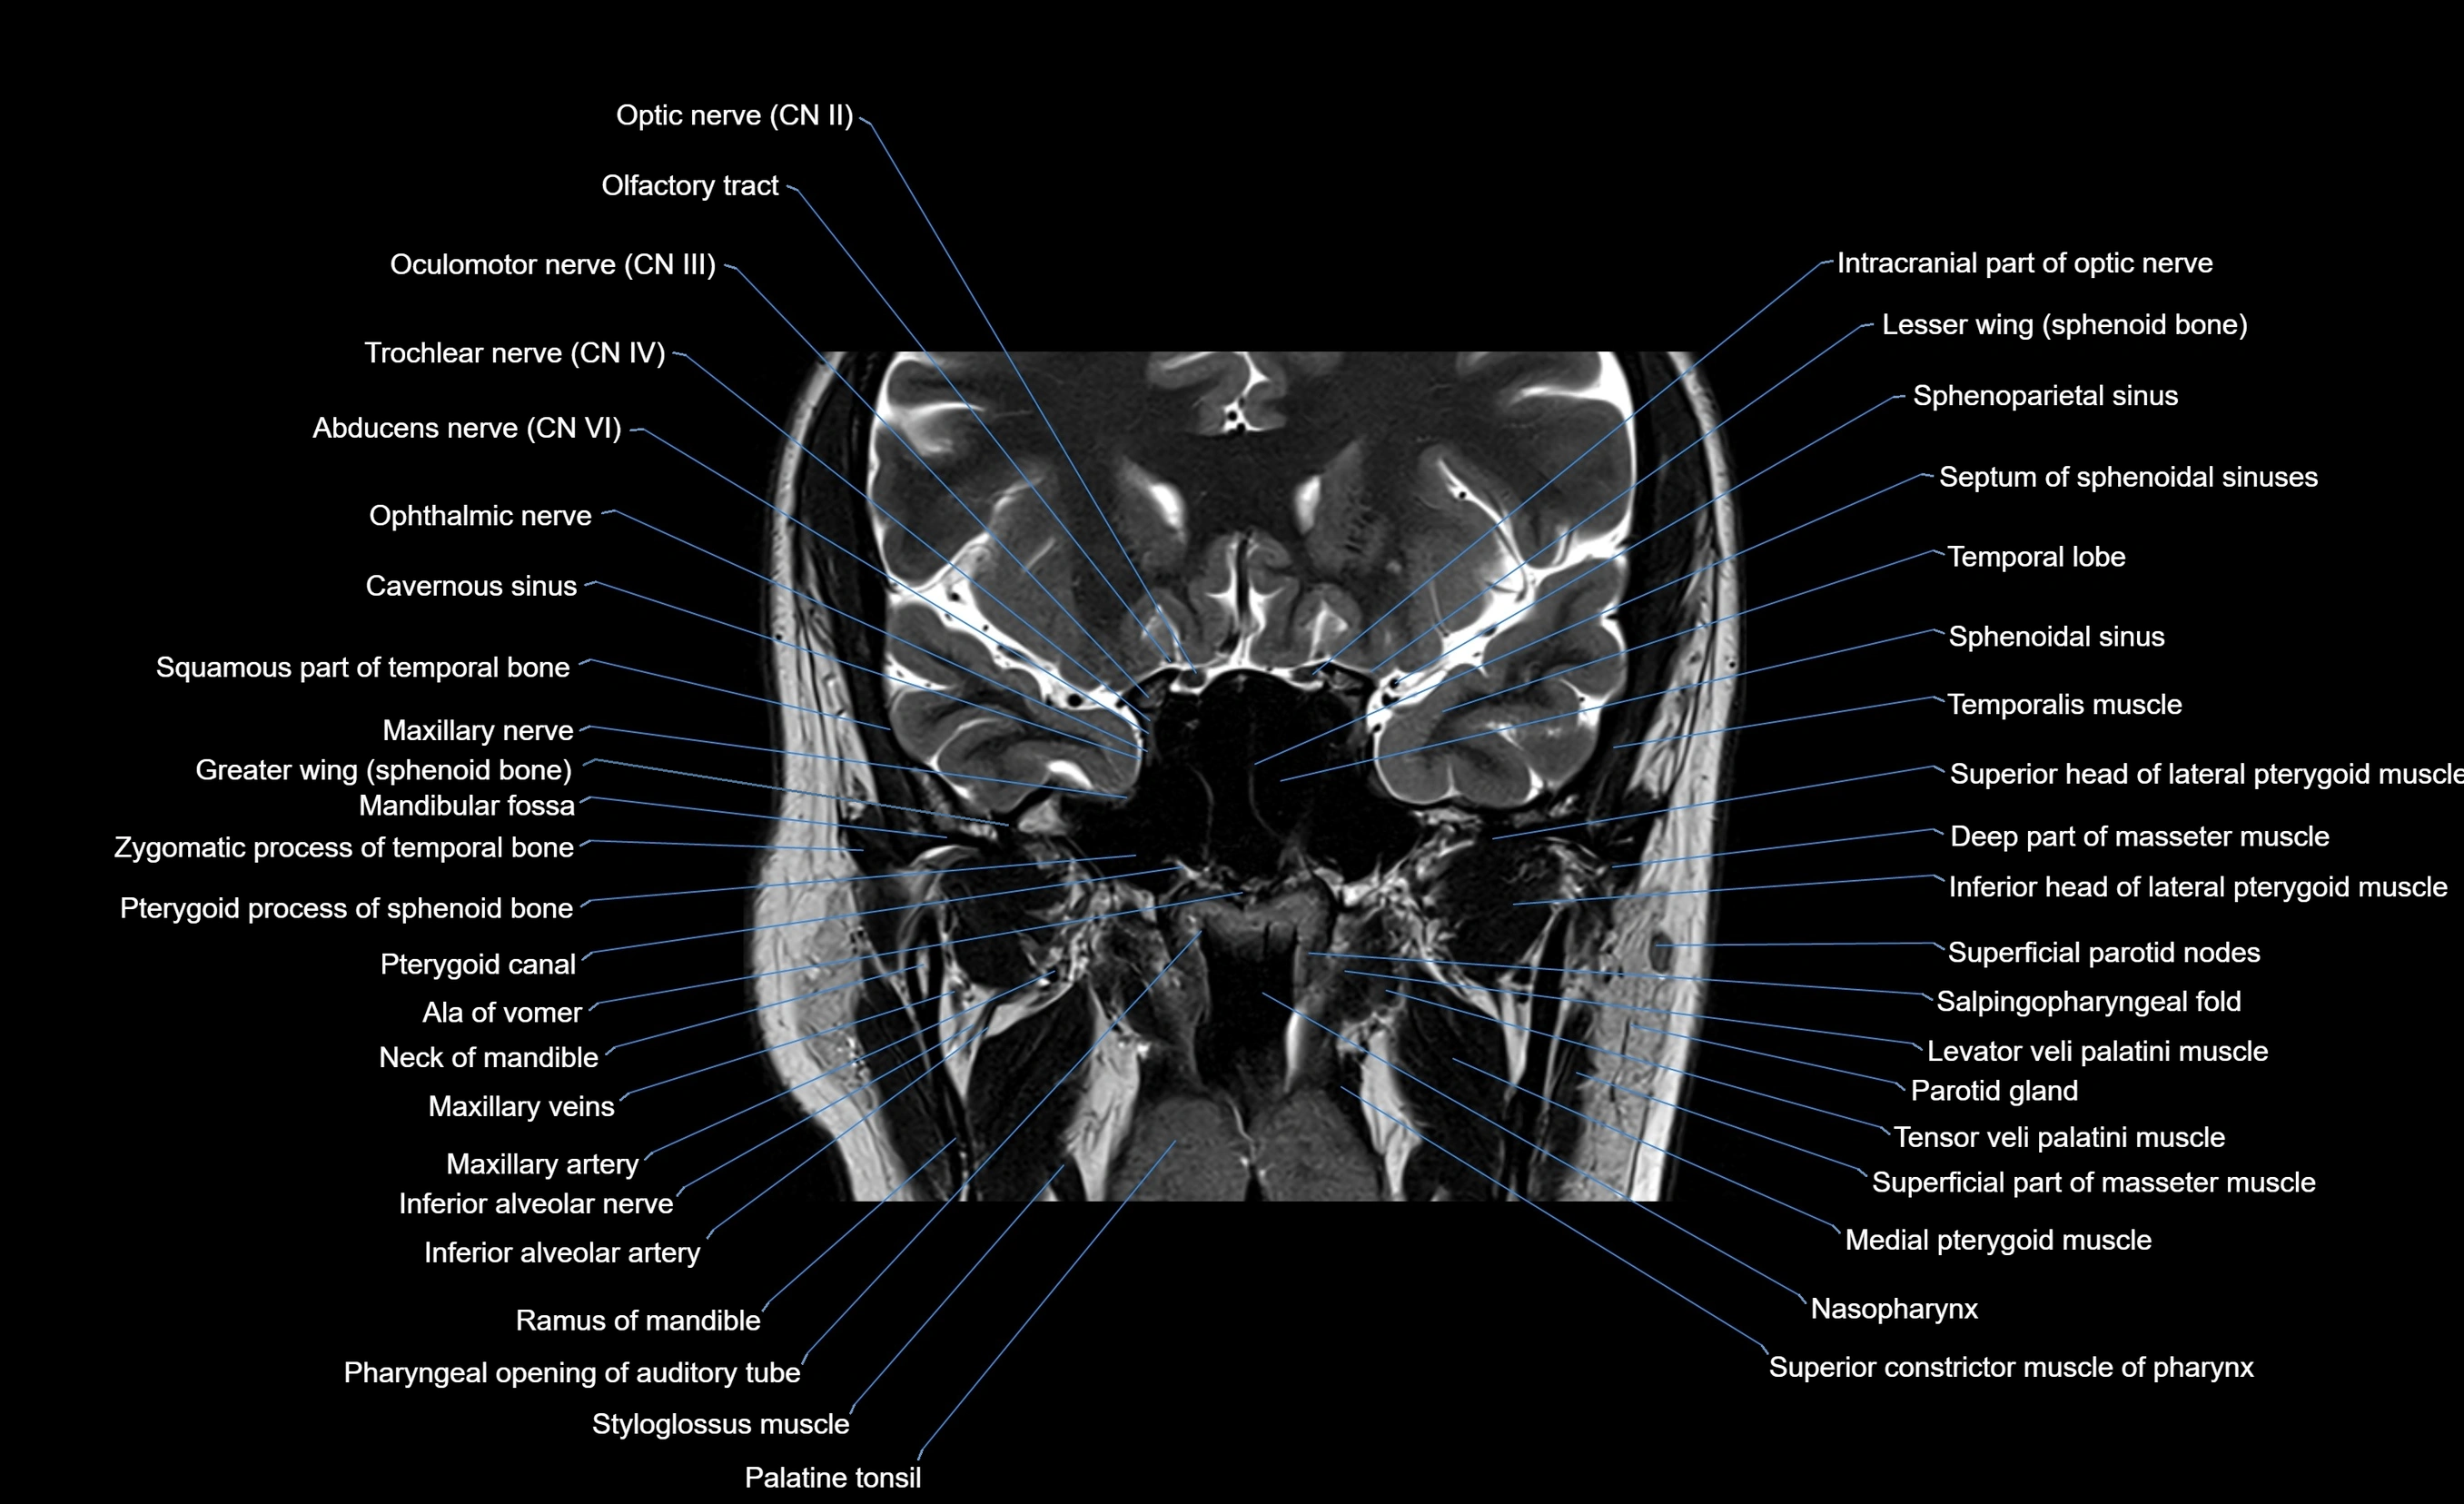

MRI images